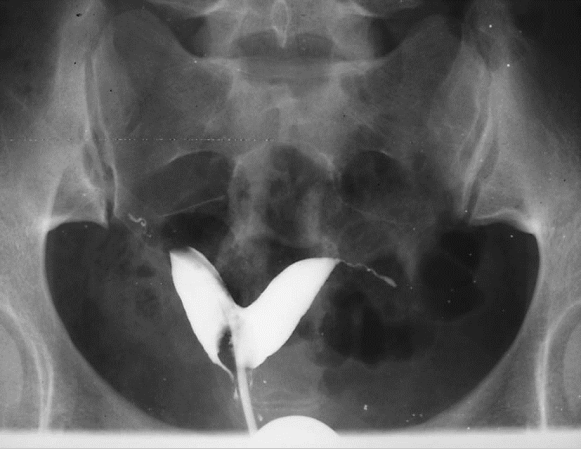

图22-1 处女膜闭锁并阴道、宫腔积血

绝大多数患者至青春期发生周期性下腹坠痛,进行性加剧。严重者可引起肛门胀痛和尿频等症状。检查可见处女膜膨出,表面呈紫蓝色;肛诊可扣及盆腔囊性包块。偶有幼女因大量黏液潴留在阴道内,导致处女膜向外凸出、下腹坠痛而就诊。盆腔超声检查可见阴道内有积液。确诊后应及时手术治疗。先用粗针穿刺处女膜中部膨隆部,抽出陈日积血后再进行“X”形切开,排出积血;常规检查宫颈是否正常,切除多余的处女膜,修剪处女膜,再用可吸收缝线缝合切口边缘。